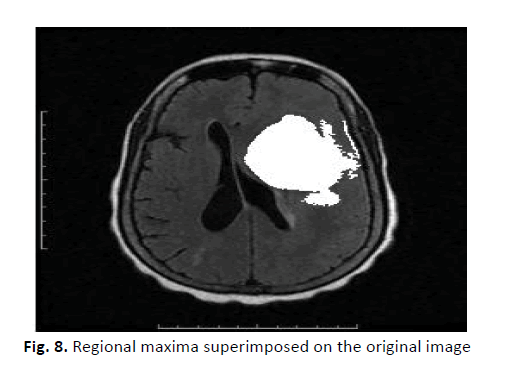

Figure 6 shows image reconstruction results of the registered MRI images and the fusion of the segmented GTV within the original image. Table 1 presents the segmentation quality, Dice similarity coefficient, and sensitivity and specificity evaluations. The segmentation quality values in all the patients ranging from 0.81 to 0.87 are higher or more similar to the average global FLAIR segmentation potential. The Dice similarity coefficient values range from 0.84 to 0.96. The mean Dice similarity coefficient is 0.92 (± 0.09), and is very consistent across the semiautomatic and manual segmentation methods. The sensitivity and specificity were 0.94 (± 0.06) and 0.90 (± 0.09), respectively, indicating that GTVs are effective in brain tumour segmentation compared to the manually defined ground-truth images (Figures 7-9).

Figure 8: Regional maxima superimposed on the original image